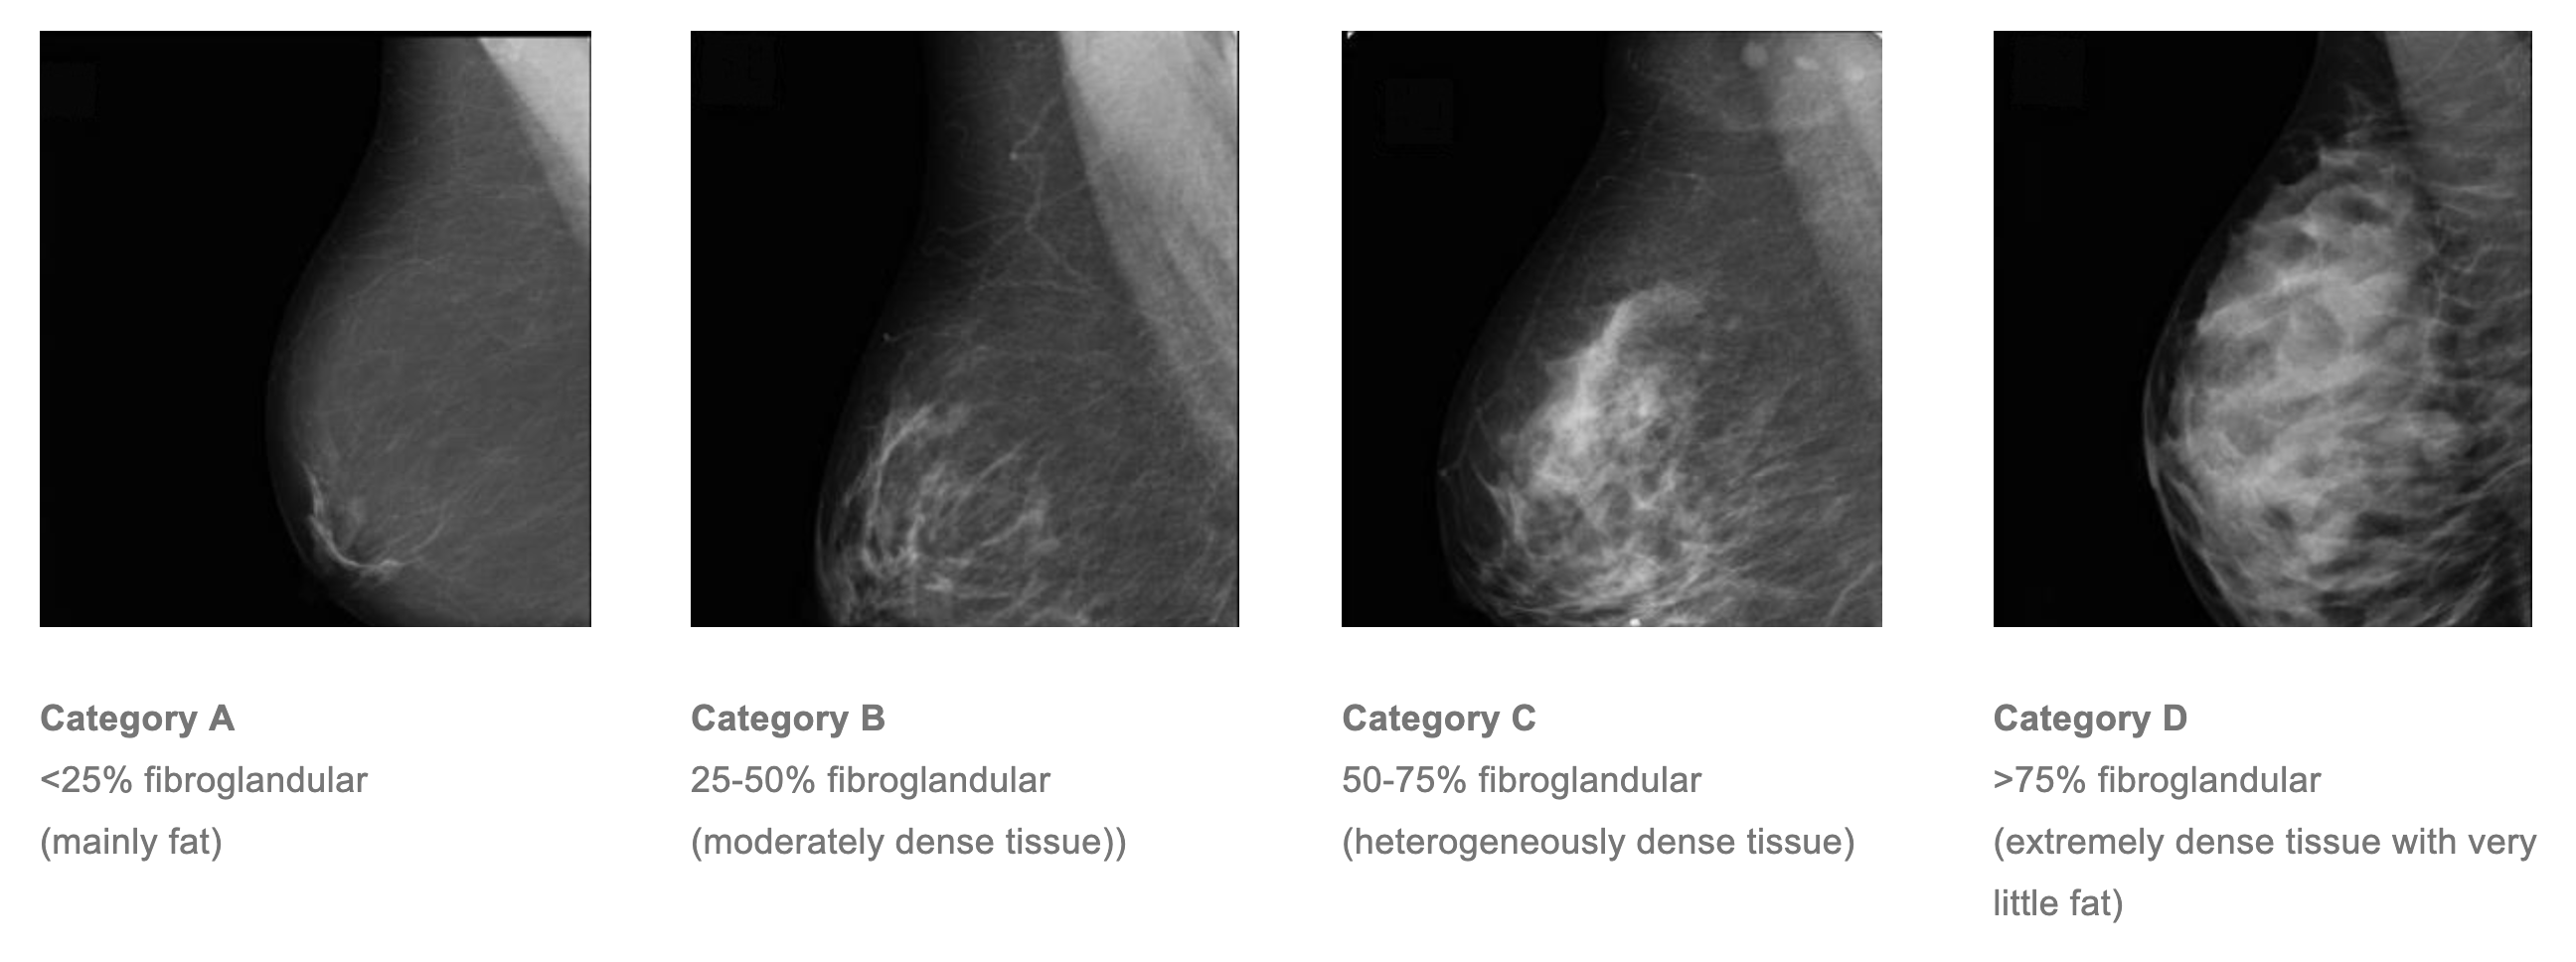

On a mammogram the breast is made up of dark areas (fat) and light areas (glandular and fibrous tissue).

The Royal Australian and New Zealand College of Radiologists and Cancer Australia recommend that mammographic breast tissue density be routinely reported, and categorised in quartiles of area percentage density1:

Research2 shows that a woman with extremely dense breast tissue has approximately five times greater risk of breast cancer than a woman with breast tissue density of <10%, all other factors being equal.

Both breast cancers and benign breast lesions (such as cysts and fibroadenomas), appear as white masses on a mammogram. They are therefore difficult to detect if the background breast tissue is also white (ie. fibroglandular) rather than fatty.

We use the mammographic density to guide the use of ultrasound examination. All women with category C or D mammographic density will be recommended a bilateral ultrasound examination following their mammogram and clinical examination, even if they are asymptomatic, and even if the tomogram showed no signs of malignancy. This is because we know that significant lesions may be obscured on mammography by general breast tissue density.